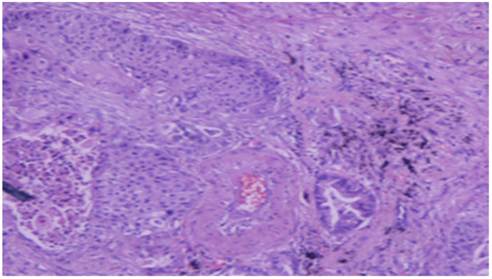

Figure 4

Squamus cell carcinoma x20